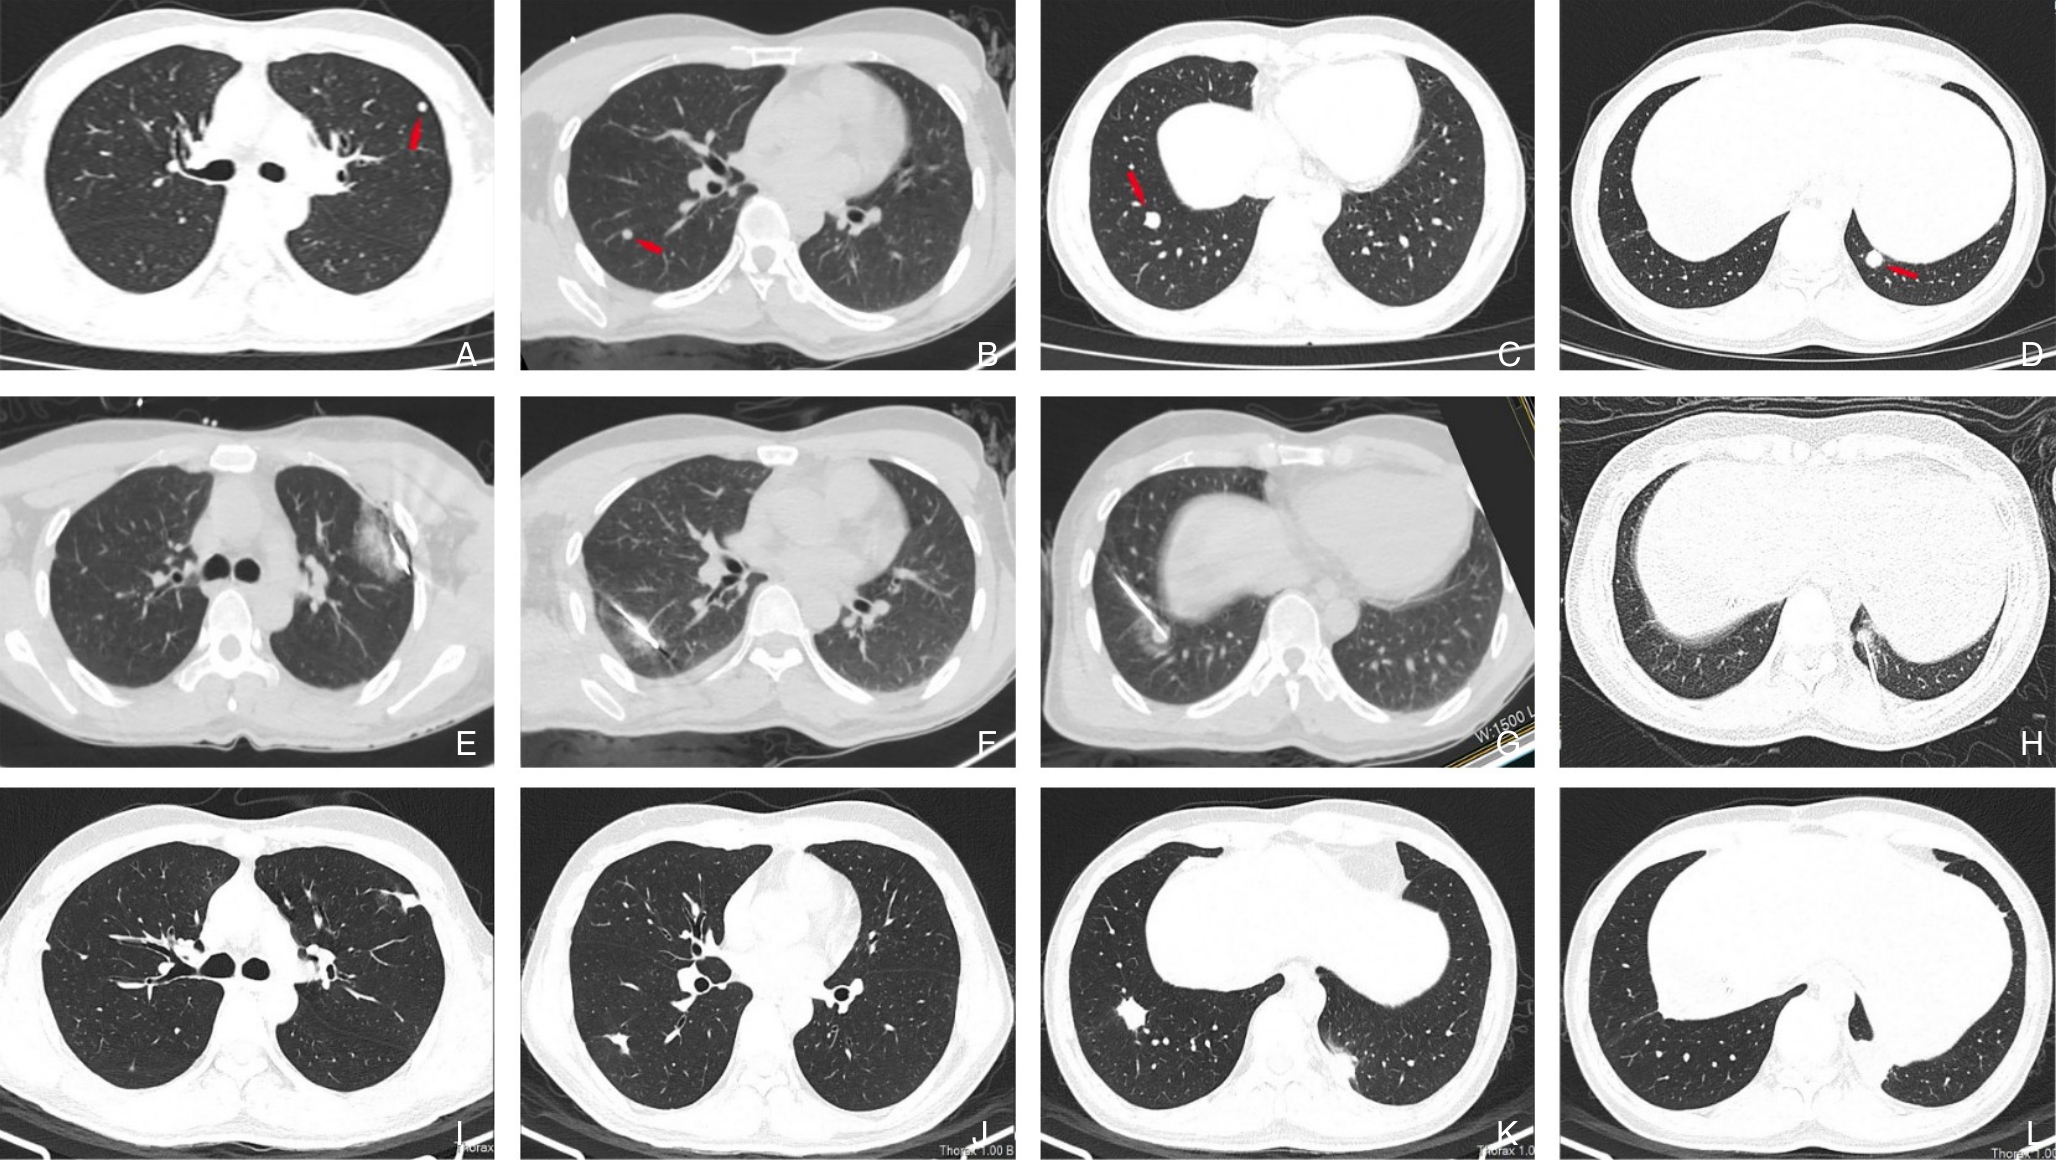

摘要:背景与目的 恶性黑色素瘤常见于皮肤及眼部等部位,肝脏原发极为罕见,且缺乏特异性临床与影像学特征,易被误诊。本文报告1例肝脏原发性黑色素瘤(PHM),并结合文献回顾分析其临床特点、诊疗策略及预后。方法 回顾性分析1例经手术切除并病理确诊的PHM患者,检索中国知网、万方、维普及PubMed数据库相关病例,共纳入42例进行总结。结果 患者,男性,61岁,术前误诊为肝细胞癌,术后免疫组化示HMB45、Melan A、SOX10强阳性,确诊为PHM。行手术完全切除肿瘤,术后12个月复发并多发转移。文献分析显示,PHM多见于中老年男性,临床表现不典型,影像学缺乏特异性,确诊依赖病理及免疫组化。预后较差,25例有随访资料的患者中,6个月和12个月生存率分别为28.00%和12.00%。结论 PHM是一种罕见且预后不良的恶性肿瘤,早期诊断困难。手术切除仍是局限性病灶的首选治疗,结合分子靶向及免疫治疗可望改善生存;失去手术机会时,应优先考虑免疫治疗和靶向治疗的个体化方案。